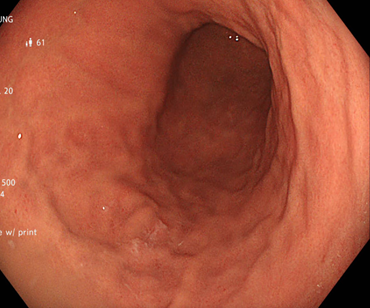

Sau điều trị diệt vi khuẩn H.pylori, tình trạng đi ngoài của BN cải thiện rõ rệt, mỗi ngày chỉ còn đi ngoài khoảng 2-3 lần, phân đã thành khuôn và hết cảm giác không hết phân sau đại tiện.

Người bệnh được tiến hành nội soi đại tràng với kết quả: các tổn thương lồi ở đại trực tràng đã biến mất, niêm mạc đại trực tràng bình thường

Hình 3: Hình ảnh đại tràng sigmoid và trực tràng sau điều trị

Trong trường hợp của chúng tôi, bệnh nhân có nhiễm H. pylori và hình ảnh đa polyp mũ đại tràng trên nội soi. Sau khi điều trị theo phác đồ 4 thuốc trong 2 tuần (Tetracyclin 2g/ngày, Tinidazol 1,5g/ngày, Esomeprazol 80mg/ngày, Bismuth 480mg/ngày), bệnh nhân đạt được sự thoái lui hoàn toàn của tổn thương polyp và cải thiện rõ triệu chứng lâm sàng.